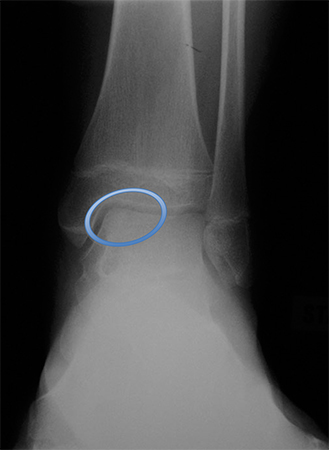

Osteochondral lesion of medial talus

From the collection of H. Chambers, MD